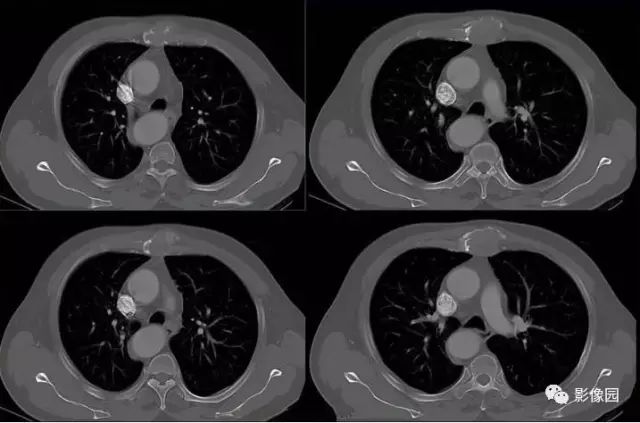

肚肚丫头: 胸骨体局部呈膨胀性骨质吸收破坏,内呈软组织密度影,可见点状钙化,增强扫描呈轻度强化,周围软组织略肿胀。考虑:1.骨巨细胞瘤;2.浆细胞瘤;3.嗜酸性肉芽肿

CT表现:特征性穿凿状、鼠咬状及蜂窝状骨破坏,边缘清楚,骨质疏松,病理性骨折及软组织肿块等表现,骨质硬化及骨膜反应少见。

骨破坏区完全为软组织取代,骨质膨胀,边界清楚,常突破骨皮质形成软组织肿块。增强扫描可见病灶轻中度强化,一般于静脉期达峰值。